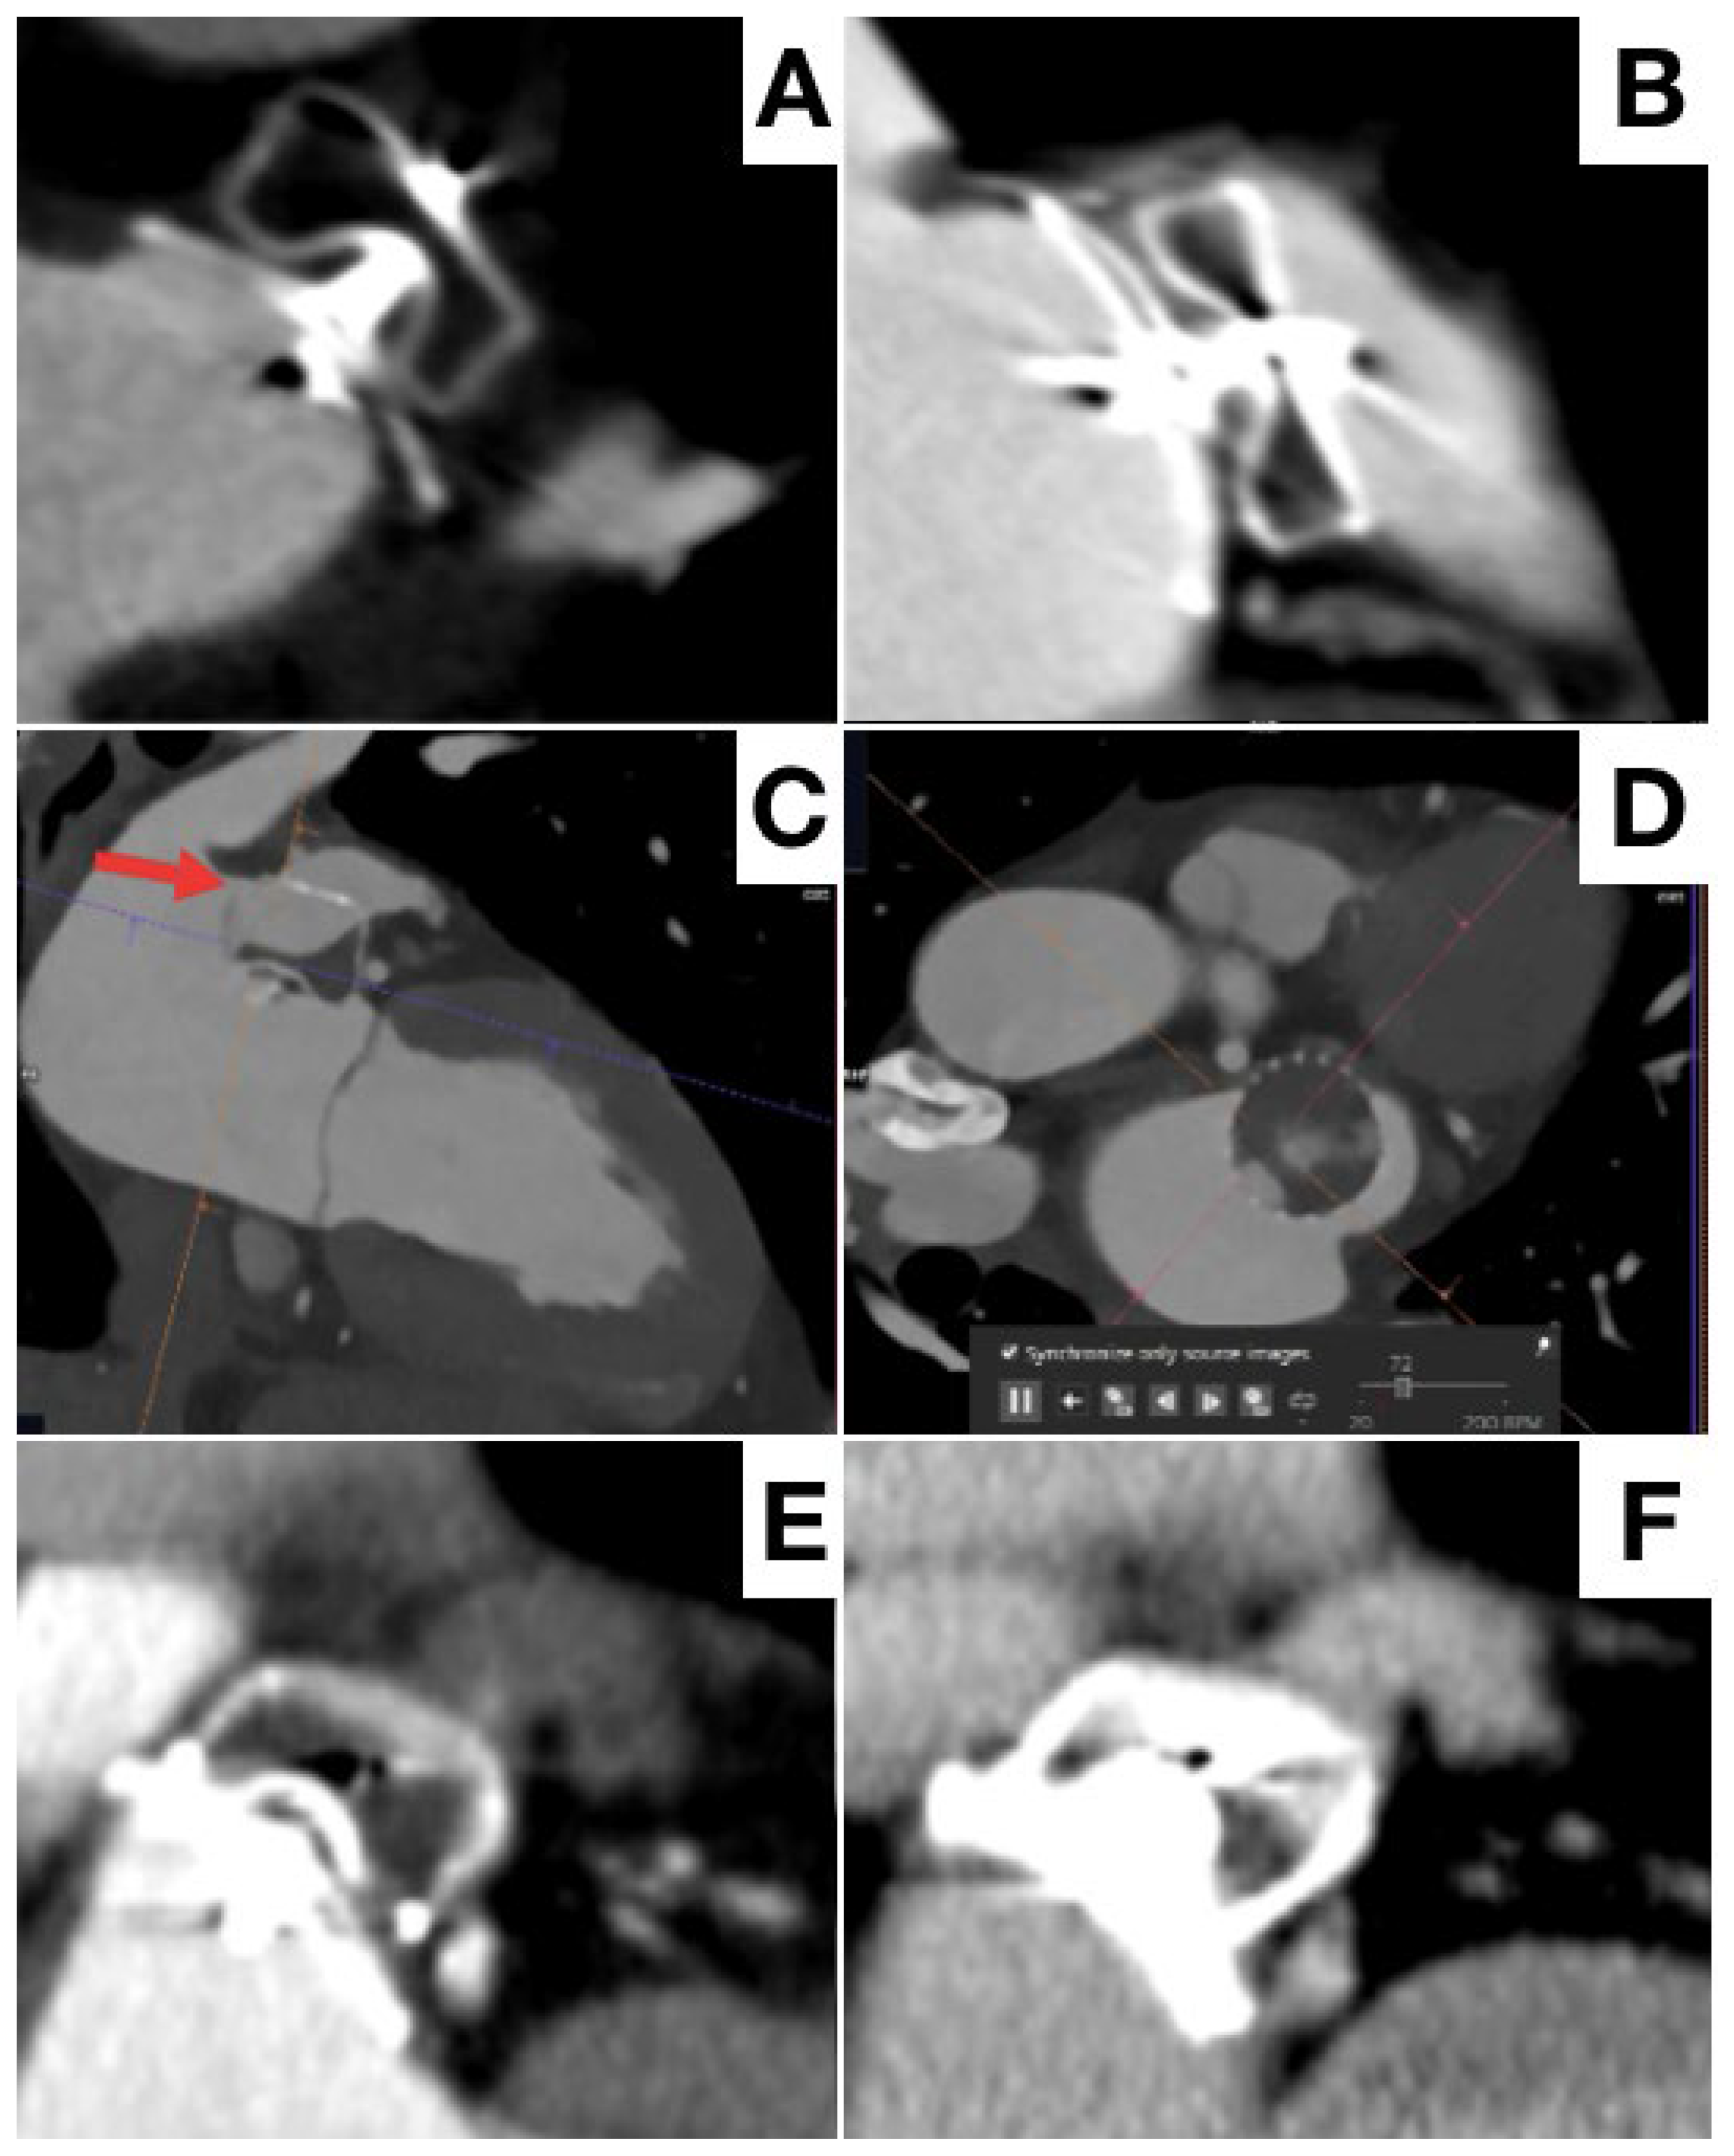

- Korsholm, K.; Jensen, J.M.; Nørgaard, B.L.; Nielsen-Kudsk, J.E. Detection of Device-Related Thrombosis Following Left Atrial Appendage Occlusion: A Comparison Between Cardiac Computed Tomography and Transesophageal Echocardiography. Circ. Cardiovasc. Interv. 2019, 12, e008112. [Google Scholar] [CrossRef] [PubMed]

- Korsholm, K.; Jensen, J.M.; Nørgaard, B.L.; Samaras, A.; Saw, J.; Berti, S.; Tzikas, A.; Nielsen-Kudsk, J.E. Peridevice Leak Following Amplatzer Left Atrial Appendage Occlusion: Cardiac Computed Tomography Classification and Clinical Outcomes. JACC Cardiovasc. Interv. 2021, 14, 83–93. [Google Scholar] [CrossRef]

- Fukutomi, M.; Fuchs, A.; Bieliauskas, G.; Wong, I.; Kofoed, K.F.; Søndergaard, L.; De Backer, O. Computed tomography-based selection of transseptal puncture site for percutaneous left atrial appendage closure. EuroIntervention 2022, 17, e1435–e1444. [Google Scholar] [CrossRef]